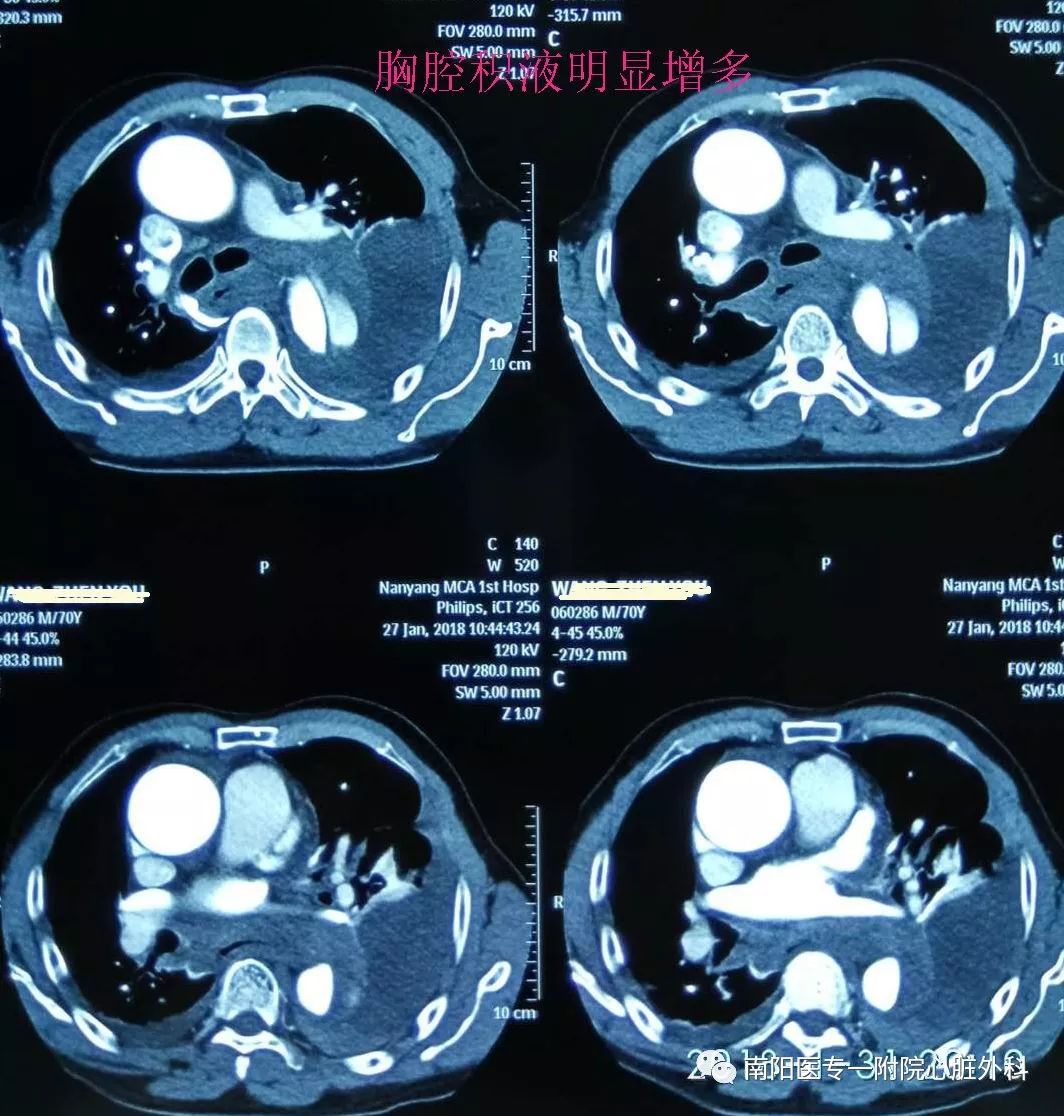

立即行CTA,明确诊断为Stanford B 型主动脉夹层,破口位于左锁骨下动脉根部,并且主动脉弓部明显增宽,左侧胸腔大量积液。此种情况非常危险,为主动脉夹层濒临破裂的征象,随时有发生破裂死亡的可能。

由于患者主动脉弓支架锚定区直径近36mm,需要大型号的支架,整个南阳市内没有,经联系只有郑州有,大雪封路,没有班车及快递,马上启动应急预案,连夜从郑州坐火车把支架运回,在住院第二天上午急诊手术,行腋腋动脉转流+主动脉覆膜支架植入+左锁骨下动脉弹簧圈封堵术,术后患者恢复顺利。